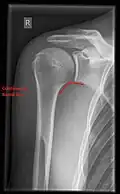

X-ray

Projectional radiography views of the shoulder include:

- AP-projection 40° posterior oblique after Grashey

The body has to be rotated about 30 to 45 degrees towards the shoulder to be imaged, and the standing or sitting patient lets the arm hang. This method reveals the joint gap and the vertical alignment towards the socket.[26]

-

CR. shoulay film. -